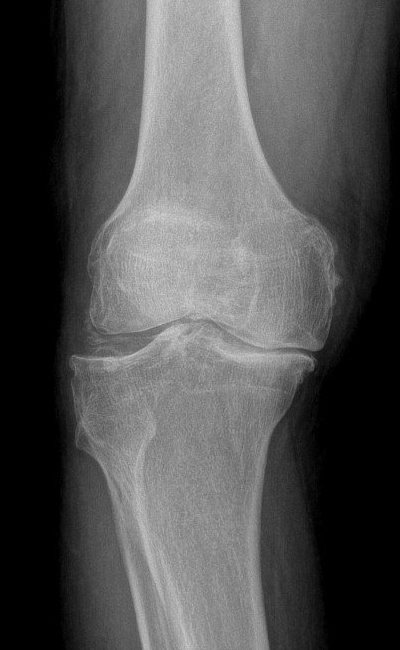

- Mais de 14 anos de experiência na especialidade de Ortopedia e Traumatologia.

- Mais de 200 cirurgias artrocópicas do joelho por ano.

- Mais de 150 reconstrucções do ligamento cruzado por ano.

- Mais de 200 próteses do joelho por ano.